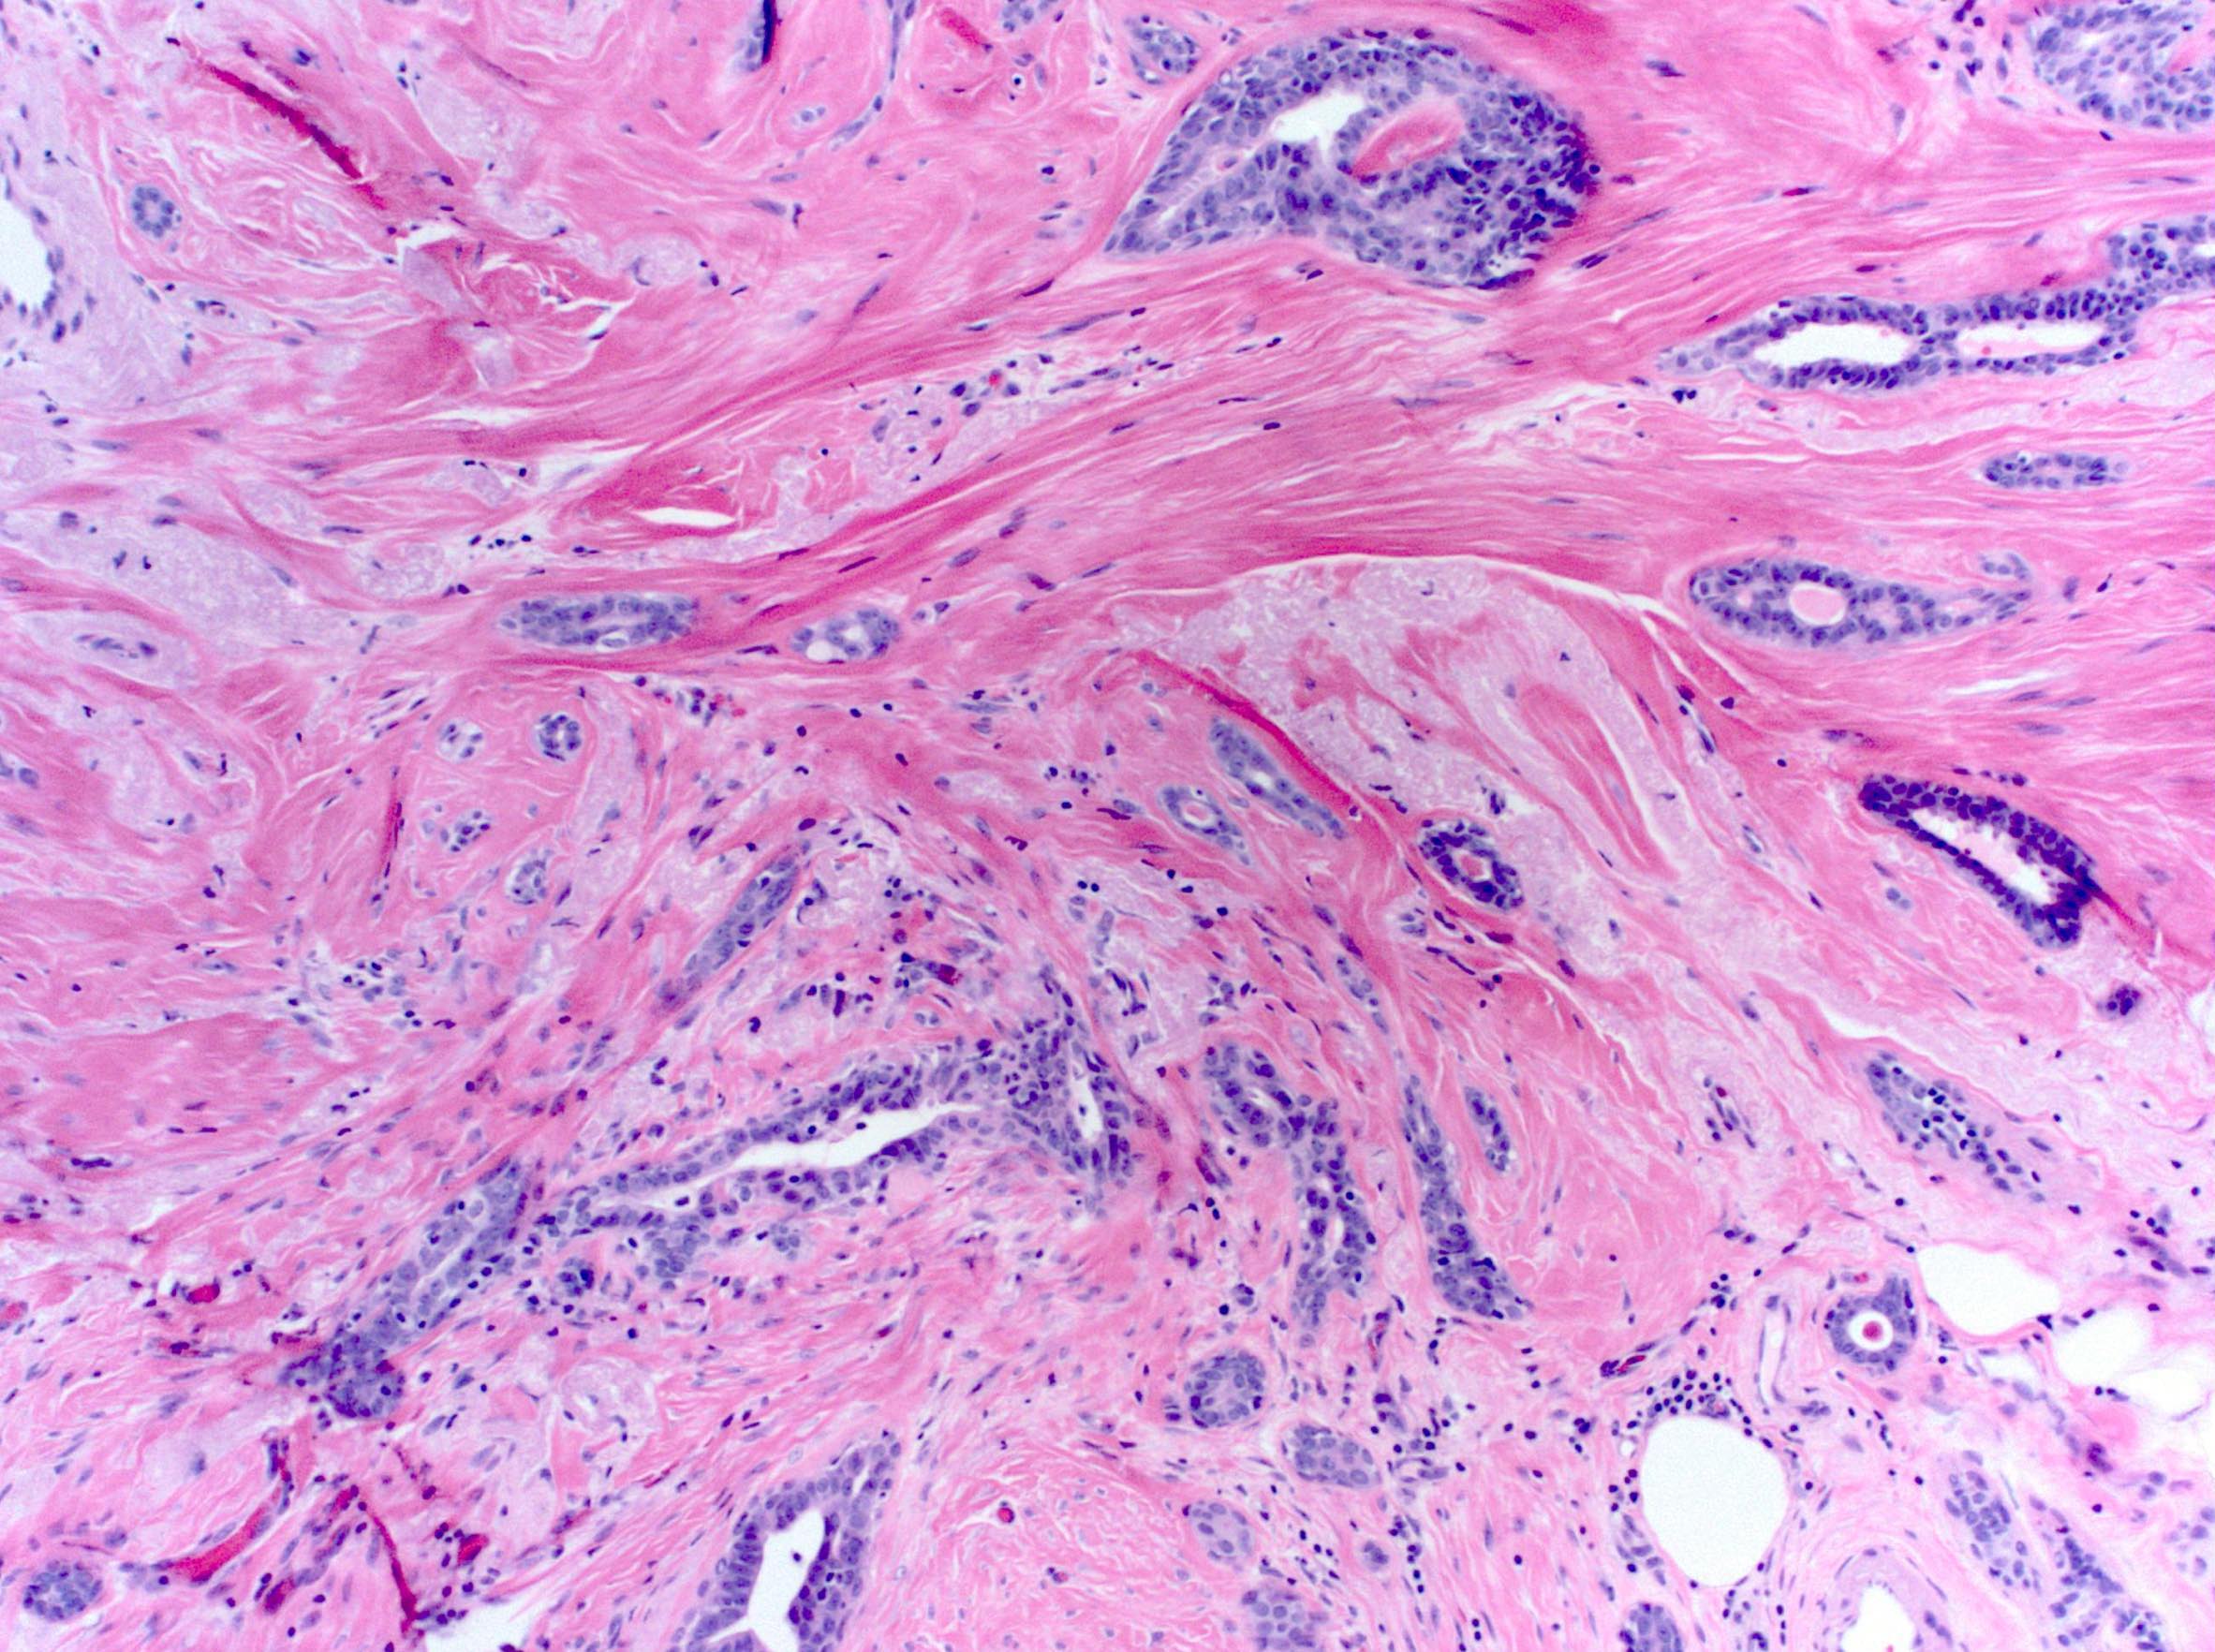

Microscopic (histologic) description

- Low power stellate configuration

- Central sclerotic zone composed of fibrosis and elastosis with ducts and lobules radiating outward between bands of sclerotic tissue

- Central core frequently contains small entrapped obliterated ductules that may mimic invasive carcinoma; squamous metaplasia may occur in central nidus

- Variable amounts of usual ductal hyperplasia (may be florid with necrosis), sclerosing adenosis, apocrine metaplasia and cysts

- Stroma tends to be more cellular in early lesions and more collagenized and sclerotic with abundant elastin in older lesions

Microscopic (histologic) images

Contributed by Kristen E. Muller, D.O.